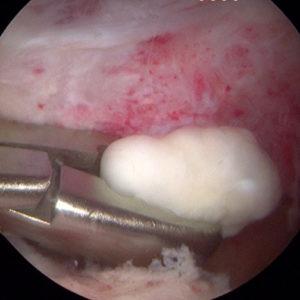

В процессе хрящевой метаплазии клетки синовиальной оболочки превращаются в узелки. Эти узелки могут образовывать плотные бугорки или иметь вид полипов на ножке, которые со временем отделяются от основной ткани и становятся свободными внутрисуставными телами, известными как «суставная мышь».

На изображении ниже представлено скопление хондромных тел в полости сустава.